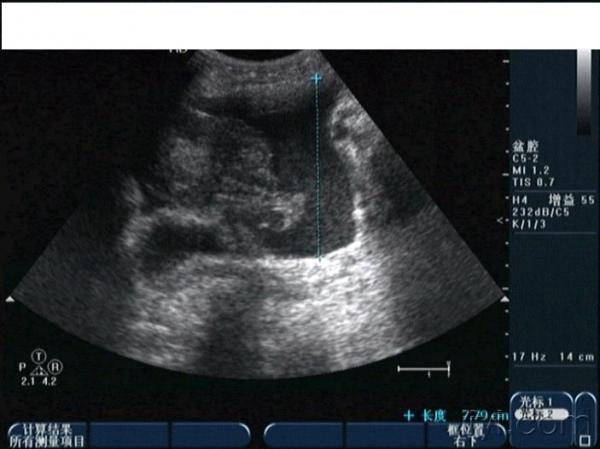

早孕并黄体破裂

晚上房事后腹痛入院,第二天早晨8点多超声所见如下,手术证术为黄体破裂。